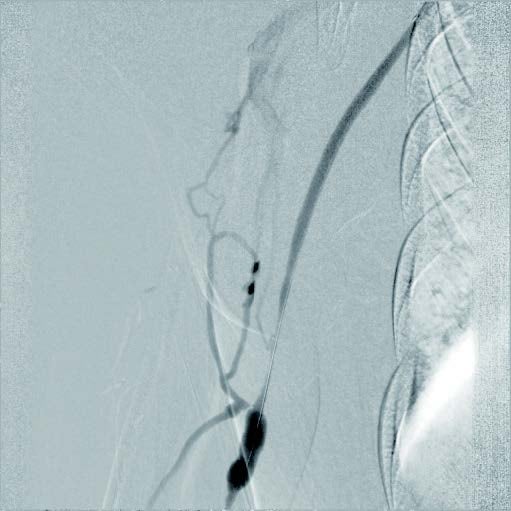

実際の治療

バイアバーン® ステントグラフト留置の手技については、当施設では概ね毎回同じ手技を実施している。ステントグラフトの長さについては病変に依存するが、径については6 mmの人工血管に対して、7 mmのバイアバーン® ステントグラフトを留置している。

静脈とはいえ、透析患者においては硬化性変化が強い病変が多く、indentation を残さずに pre dilatation をかけておくことが重要と考えられる。そこで、径7 mmのバイアバーン® ステントグラフト留置前に、径6 mmの高耐圧バルーンにてしっかり拡張し、indentationを残さないことを確認した。バイアバーン® ステントグラフト留置後もバルーンでステント内、特に人工血管とのオーバーラップ部位にしっかり圧をかけて後拡張を行っている。

また、バイアバーン® ステントグラフトは、位置決めをした後の留置時に移動する事象は自施設で行った症例ではほとんど認めていないが、展開時のstabilityを保つため0.018 inchのサポートワイヤーを用いることが多い。当患者においても、上記手技を行い良好なinitial successを得られた。他症例もほぼ同一の手技で行っているがサイズなどで問題になった症例は、本稿の執筆時点では経験していない。